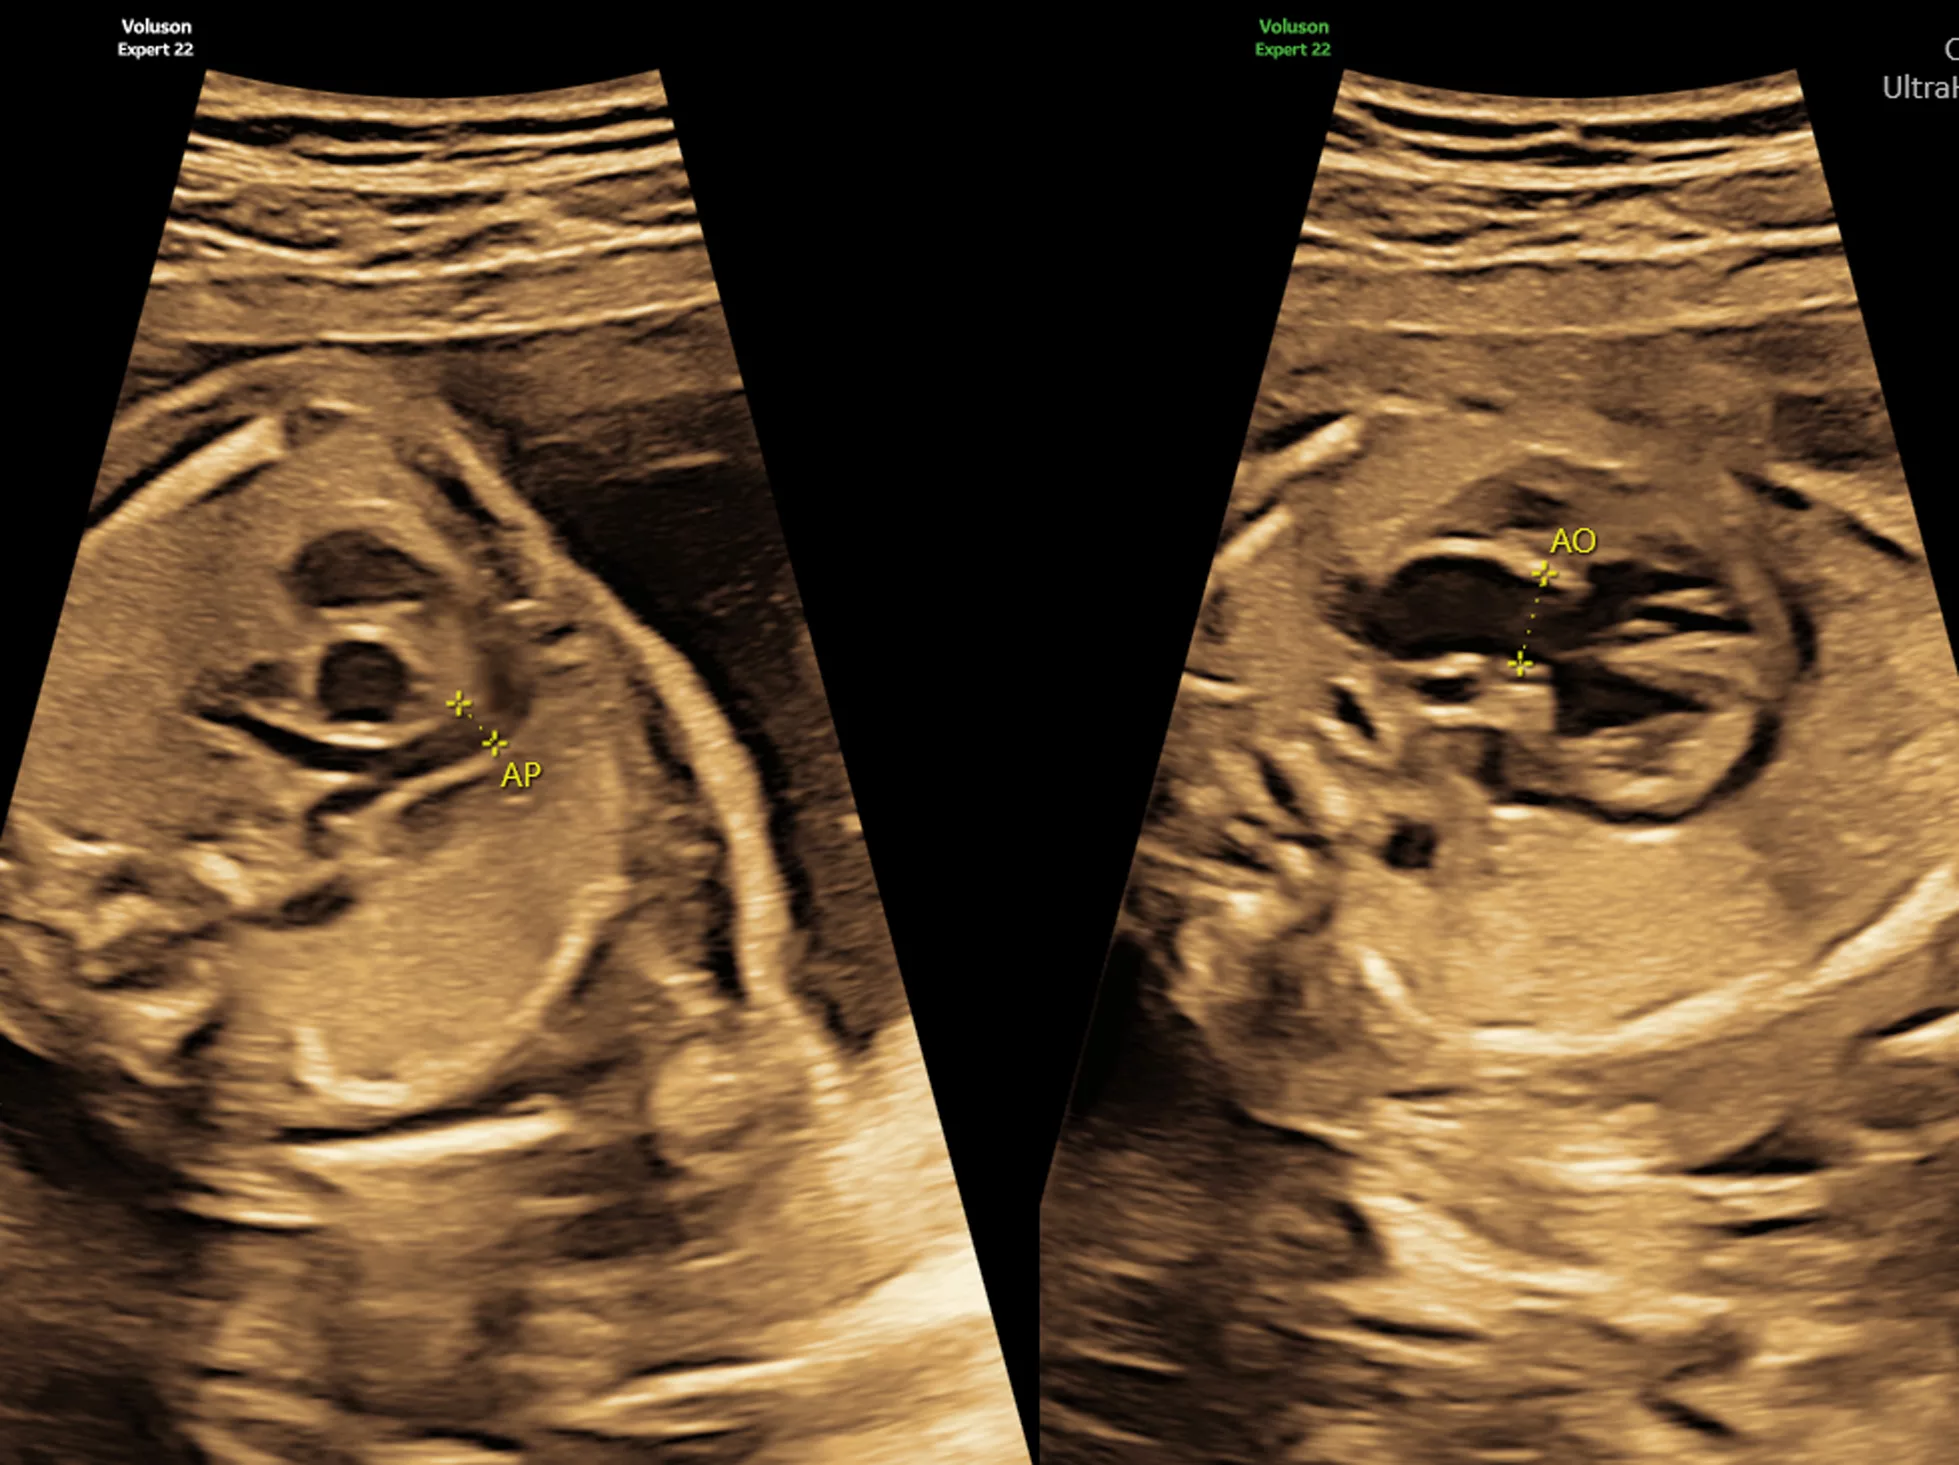

- Prenatal assessment of the antero-posterior jaw relationship in human fetuses: from anatomical to ultrasound cephalometric analysis. Captier G, Faure JM, Bäumler M, Canovas F, Demattei C, Daures JP. Cleft Palate Craniofac J. 2010 Jul 1.

- Prenatal assessment of the normal fetal soft palate by three-dimensional ultrasound examination: is there an objective technique? Faure JM, Bäumler M, Boulot P, Bigorre M, Captier G. Ultrasound Obstet Gynecol. 2008 Jun;31(6):652-6

- Sonographic assessment of normal fetal palate using three-dimensional imaging: a new technique. Faure JM, Captier G, Bäumler M, Boulot P. Ultrasound Obstet Gynecol. 2007 Feb;29(2):159-65.